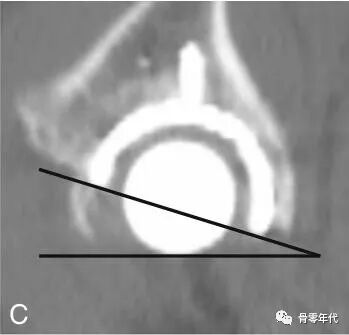

髋臼杯前倾角(C)定义为在矢状面上测量的前倾角